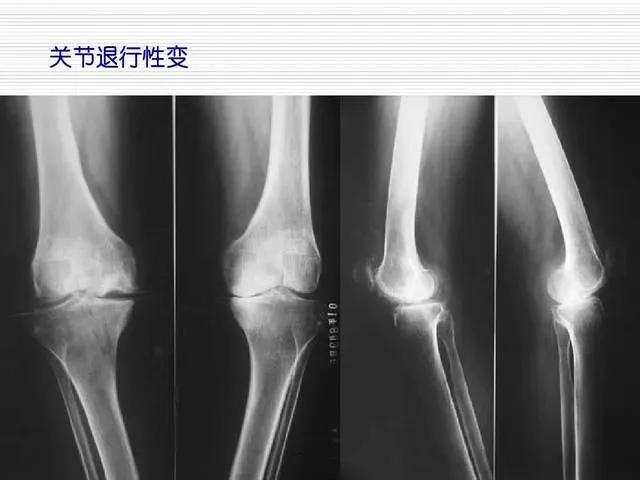

我们先看看,老人究竟得了什么病?骨性关节炎,这是在中老年人中很常见的慢性骨关节退变疾病。

因为后来她骨折的时候,住院期间,拍了X片,发现结合她的症状,疾病变化规律,可以得出骨性关节炎的诊断。

1、高体重。2、中老年人。3、反复疼痛,逐渐加重,时间很长。4、双侧膝关节交替疼痛。5、早上起来和坐久了起身,关节僵硬,活动后改善,走多了又疼。6、关节有摩擦音。7、X片提示膝关节内侧间隙变窄。8、反复肿胀。

而陈大妈的罗圈腿,也是骨性关节炎的后期表现,他们这些老年人,几乎不可能让她按照上述的要求进行治疗,做不到。